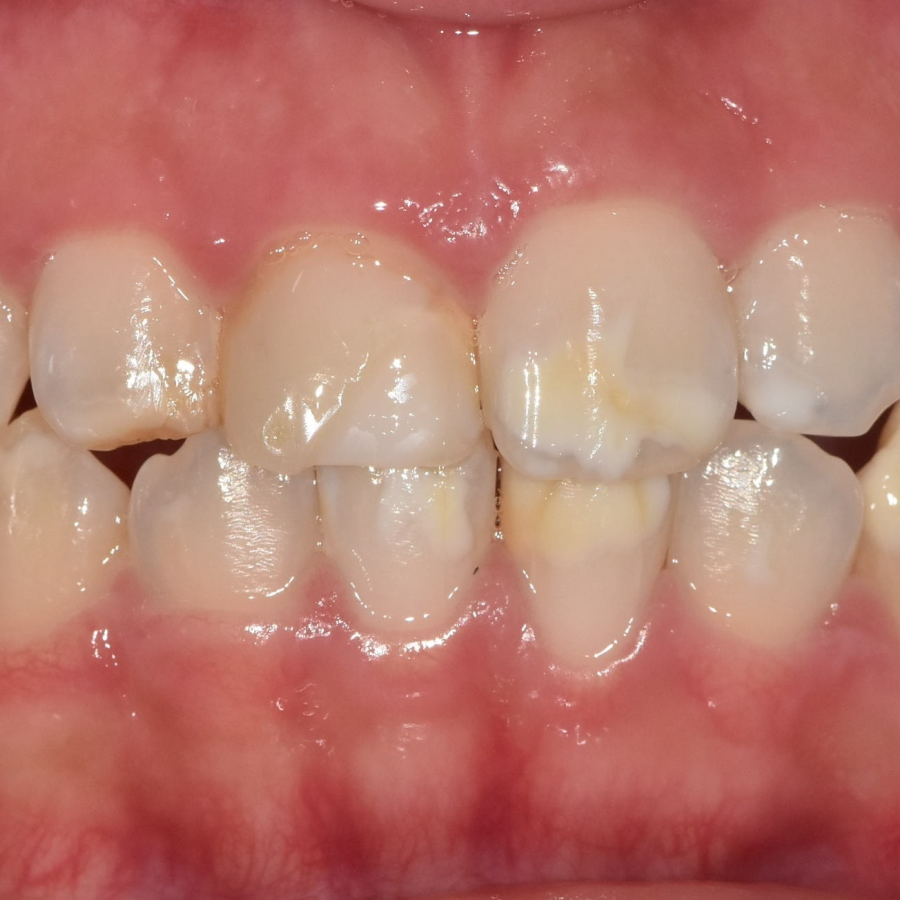

이 환자분은 하얀 반점 때문에

마음대로 웃지도 못한다고 하셨어요.

입안을 보니, 하얀 반점이 치아의 절반 이상을 덮을 만큼 퍼져 있습니다.

치아 절반 이상을 덮은 하얀 반점